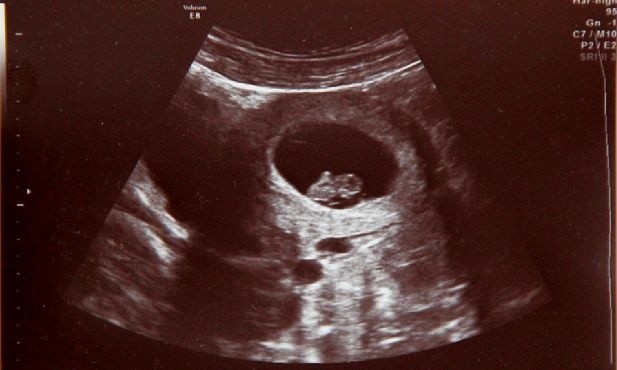

Do niedawna poważne wady płodu oznaczały dramat i brak nadziei. Postęp perinatologii sprawił, że lekarze diagnozują i leczą dzieci w łonie matki - powiedział prof. Przemysław Kosiński. Ale żeby leczyć, trzeba rozpoznać. Dlatego zaleca, by USG wykonywać co najmniej trzy razy w czasie ciąży.

- Perinatologia, czyli medycyna zajmująca się płodem jako pacjentem, rozwija się błyskawicznie. Dzięki miniaturyzacji sprzętu, nowoczesnym aparatom USG i doświadczeniu zespołów możemy diagnozować i leczyć dzieci jeszcze przed narodzinami - powiedział prof. Przemysław Kosiński, kierownik Oddziału Klinicznego Położnictwa, Perinatologii, Ginekologii i Rozrodczości Uniwersyteckiego Centrum Klinicznego Warszawskiego Uniwersytetu Medycznego.

- Kluczem jest jednak diagnostyka prenatalna. Bo żeby leczyć, trzeba najpierw rozpoznać. USG jest bezpieczne i powinno być wykonywane co najmniej trzy razy w każdej ciąży. Czasem jedno badanie decyduje o tym, czy dziecko będzie żyło - podsumował specjalista.